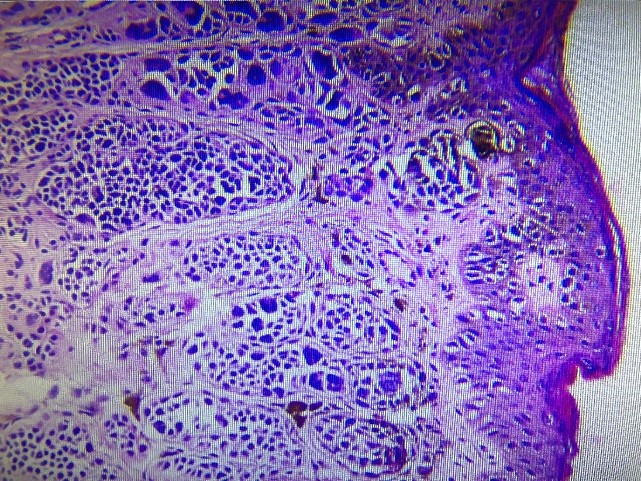

色素痣是由痣細(xì)胞構(gòu)成的良性新生物,顏色多呈深褐色或黑褐色,少數(shù)沒有顏色人稱為色素痣。痣有多種分類,最合理的方法是按照黑色細(xì)胞的位置來分,因?yàn)楹谏丶?xì)胞的位置與其惡變的可能性以及組織發(fā)生學(xué)有明確的相關(guān)性。普通型色素痣根據(jù)痣細(xì)胞與表皮真皮交界的位置關(guān)系分類,可分為:皮內(nèi)痣、復(fù)合痣、交界痣,其中交界痣最易繼發(fā)惡性黑色素瘤。

皮內(nèi)痣

復(fù)合痣